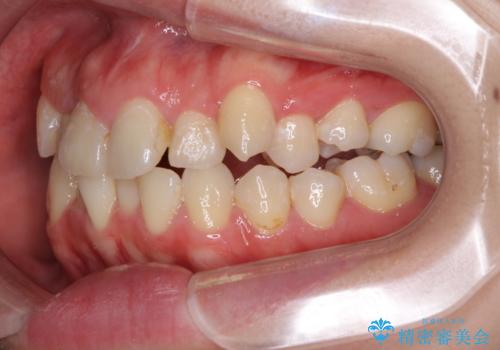

- 上下のデコボコと奥歯の咬みにくさを気にして来院された患者様です。

上顎骨の幅が下顎骨よりも小さいので、拡大装置により骨幅を広げて上下関係を改善し、その後インビザラインにて歯並びを整えることとしました。

上下の骨幅を改善したことで、スムーズに歯列矯正を行うことができました。

奥歯の咬み合わせを改善する必要があったため、治療は長期化しましたが、きっちりと仕上げることができました。